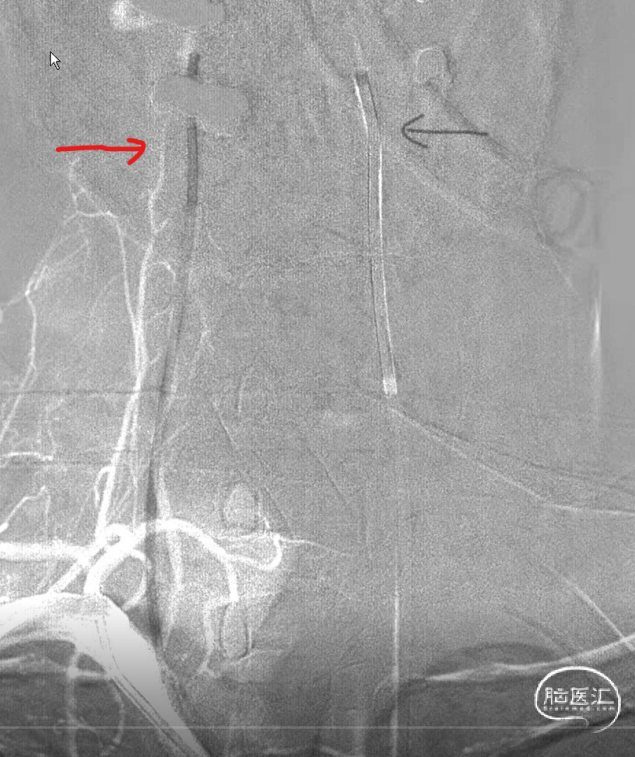

左侧为主椎,当然把6F导引导管放到左侧(黑色箭头),右侧椎稍微细一些,安排上5F的导引导管(红色箭头)。因此右侧大脑后的支架导管塑型角度稍大一些弧形,弹簧圈微导管安排S型,左侧嘛?单弯足以。

用的是可以利用弹簧圈微导管释放支架的导管。好处有:第一容易到位,即使到达大脑后动脉角度较大时也可以通过微导管塑型减少对动脉瘤的骚扰。第二支架在血管内形成血栓的概率小一些。

所以,此时如果是比较粗的导管可能对动脉瘤的张力较大,增加破裂风险,但是即使是比较细的弹簧圈微导管,也得小心翼翼通过,不得粗暴。

右侧大脑后动脉导管到位,解释一下由于远端血管条件不是太好,因此没有往更远走一些,二则,支架为无头的因此,此位置够用了。

因为在同侧所以也把弹簧圈微导管到位。虽然塑型角度比较大,可能由于血管的束缚和导管的回弹,角度感觉还是小了些,不过应该还是可以的。不过再上第三个管时,应该把前两个管锁紧。